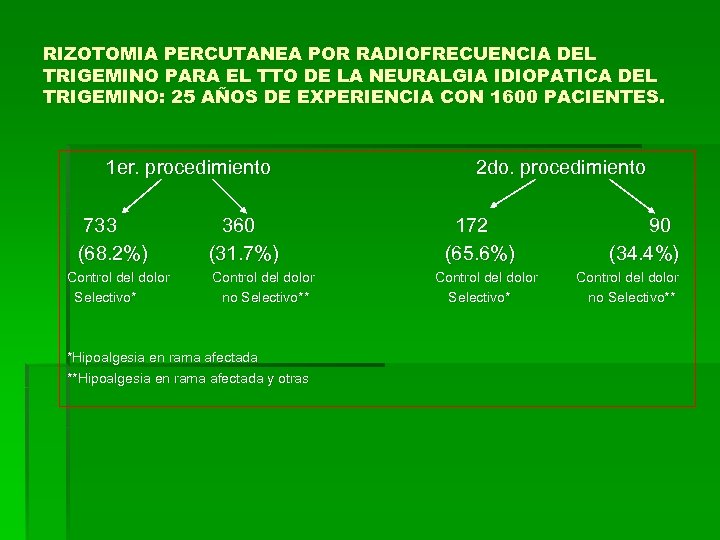

RIZOTOMIA PERCUTANEA POR RADIOFRECUENCIA DEL TRIGEMINO PARA EL TTO DE LA NEURALGIA IDIOPATICA DEL TRIGEMINO: 25 AÑOS DE EXPERIENCIA CON 1600 PACIENTES. 1 er. procedimiento 733 (68. 2%) Control del dolor Selectivo* 360 (31. 7%) Control del dolor no Selectivo** *Hipoalgesia en rama afectada **Hipoalgesia en rama afectada y otras 2 do. procedimiento 172 (65. 6%) Control del dolor Selectivo* 90 (34. 4%) Control del dolor no Selectivo**

RIZOTOMIA PERCUTANEA POR RADIOFRECUENCIA DEL TRIGEMINO PARA EL TTO DE LA NEURALGIA IDIOPATICA DEL TRIGEMINO: 25 AÑOS DE EXPERIENCIA CON 1600 PACIENTES. 1 er. procedimiento 733 (68. 2%) Control del dolor Selectivo* 360 (31. 7%) Control del dolor no Selectivo** *Hipoalgesia en rama afectada **Hipoalgesia en rama afectada y otras 2 do. procedimiento 172 (65. 6%) Control del dolor Selectivo* 90 (34. 4%) Control del dolor no Selectivo**